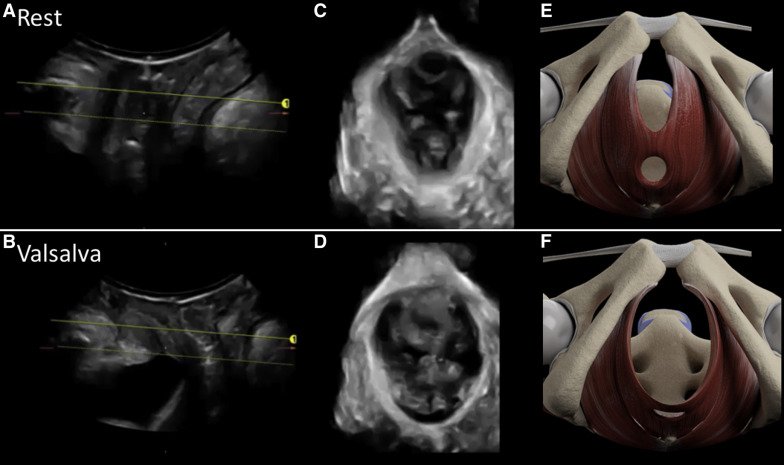

El objetivo del estudio fue evaluar el efecto de la coactivación del músculo elevador del ano sobre el resultado del parto, en particular sobre la duración de la segunda etapa activa y la segunda etapa del parto, en mujeres nulíparas sometidas a inducción del parto. La ecografía transperineal se utilizó para medir el diámetro anteroposterior del hiato del elevador, tanto en reposo como en la maniobra máxima de Valsalva, en un grupo de mujeres nulíparas sometidas a parto en 2 hospitales universitarios de nivel terciario. Se evaluó la correlación entre el diámetro anteroposterior de los valores de hiato del elevador y la coactivación del músculo elevador del ano con el modo de administración y diversas duraciones del trabajo de parto.

En total, 138 mujeres fueron incluidas en el análisis. El mayor diámetro anteroposterior del hiato del elevador en Valsalva se asoció con una segunda etapa más corta (r = –0.230, P = .021) y una segunda etapa activa (r = –0.338, P = .001) del parto. Las mujeres con coactivación del músculo elevador del ano tuvieron una duración de la segunda etapa activa significativamente más larga (60 ± 56 frente a 28 ± 16 minutos, p <0,001). El análisis de regresión de Cox, ajustado a la edad materna y la analgesia epidural, demostró una correlación significativa independiente entre la coactivación del músculo elevador del ano y una segunda etapa activa del parto más prolongada (índice de riesgo, 2.085; intervalo de confianza del 95%, 1.158–3.752; P = .014).No hubo diferencias significativas entre las mujeres que se sometieron al parto quirúrgico (n = 46) en comparación con el grupo de parto vaginal espontáneo (n = 92) en cuanto al diámetro anteroposterior del hiato del elevador en reposo y en la maniobra de Valsalva, ni en la prevalencia del levador Coactivación de los músculos del ano (10/46 vs 15/92; P = .49).

La coactivación del músculo elevador del ano se asocia con una segunda etapa activa más prolongada del parto.